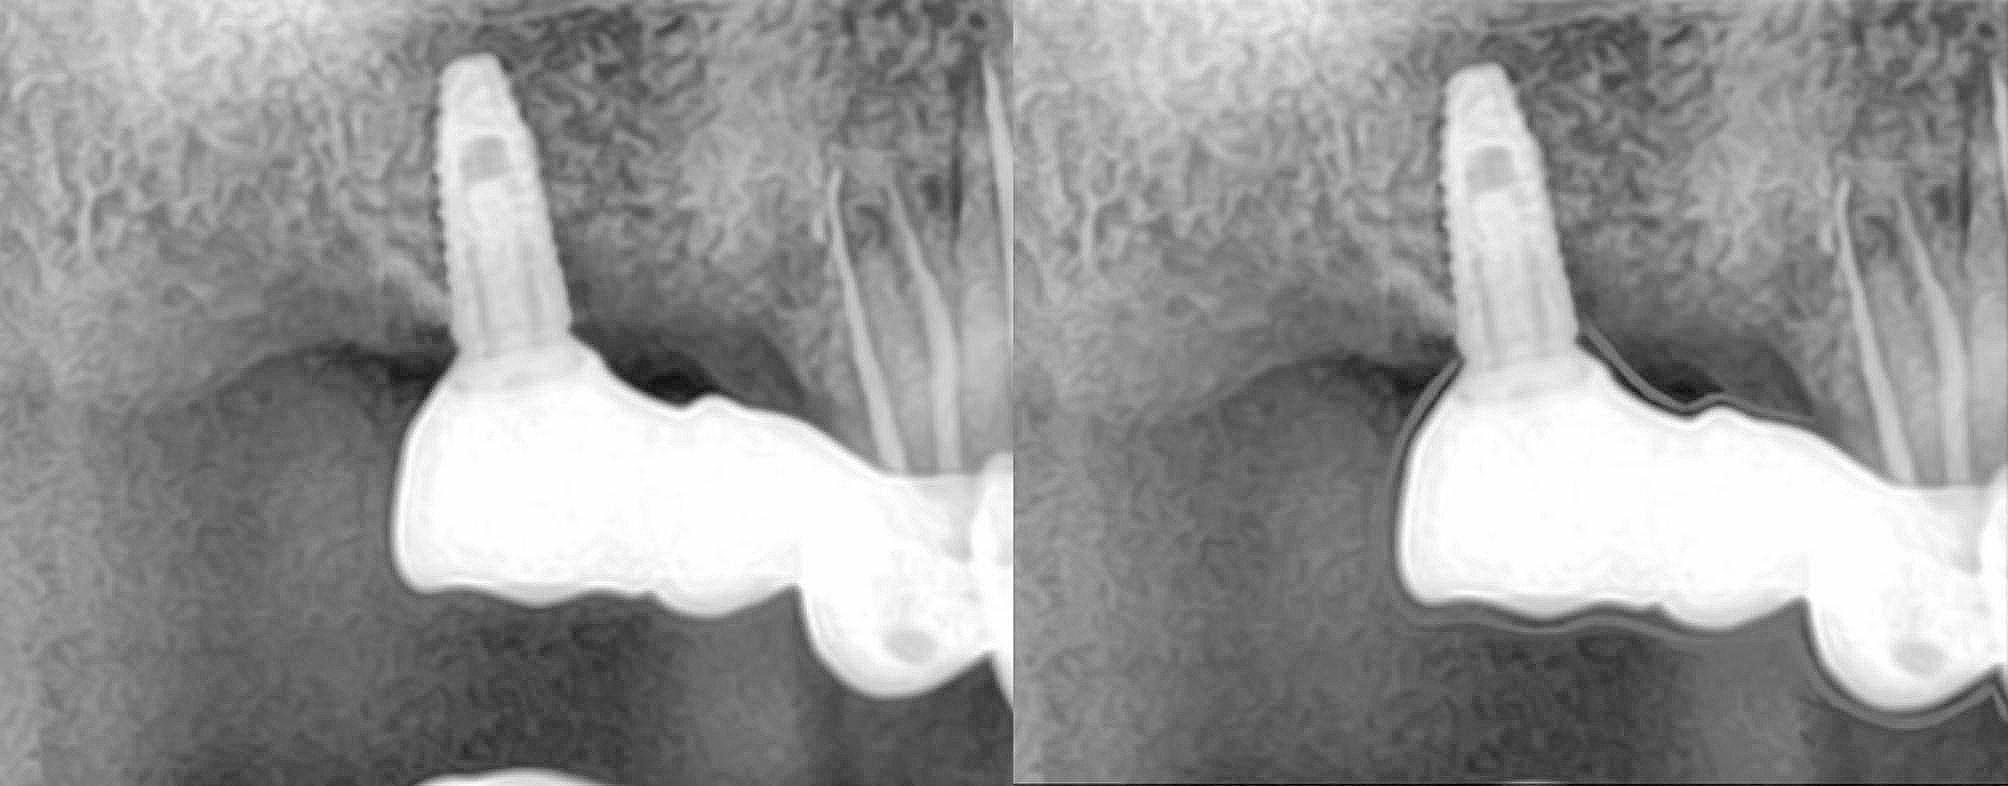

The baseline to evaluate the prosthesis was checked 7 days after the cementation. At this time, intraoral photographs were taken, probing depth was measured and a radiograph was taken to ascertain the bone level at the time of loading. The patient was recalled at timely intervals of 6 months, 12 months, 18 months and 24 months. An intraoral picture and a radiograph was taken at every appointment to compare with that at the baseline. A standardization was done for the two-dimensional radiographs which would help us in proper evaluation [14]. This made the process of evaluating the radiographic changes if any, more easier (Fig. 5).

Fig. 5.

(A) Radiograph at baseline, (B) Radiograph at 12 months showing 1mm bone loss, (C) Radiograph at 24 months showing 1mm bone loss

bone loss around implants Bone loss of 1 mm was seen around one implant at 12 months. Bone loss of 1 and 2 mm was present around two implants and one implant respectively at 24 months(Table 4).

The marginal bone loss was measured by checking the bone levels radiographically and comparing it with the condition at the time of loading. This was recorded at 12 months and 24 months. The maximum amount of bone loss seen was 2 mm at 24 months in one case where the prosthesis also showed technical complications. This could be due to improper occlusal scheme at the time of loading or heavier occlusal loads being transferred [28, 29]. In other studies that were conducted checking the marginal bone loss levels between implant supported FPDs and tooth implant supported FPDs, it was noted that the margianl bone loss was more in the implant supported group [30] and hence using the tooth and implant connection could be seen as a viable prosthetic option with good results. Secondary caries was seen in three teeth at 18 months and 24 months. One tooth was endodontically whereas two were not. The vital teeth showed caries and endodontic intervention was required for the same. No significant difference was seen between those abutments that were vital and root canal treated. Periodontal complications were not seen in any of the cases which included deep pockets or increased bleeding on probing. Patients were explained the importance of oral hygiene to be followed at home and also the importance of follow-up appointments.